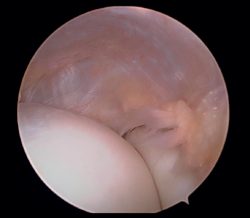

A continuación, se explora el compartimento anterior del codo en busca de sinovitis, lesiones condrales, cuerpos libres, plicas sinoviales o cualquier otra lesión, y se procede a su tratamiento mediante sinovectomía, desbridamiento, extracción o exéresis, respectivamente (Figura 6).

Figura 6. Compartimento anterior del codo, se aprecia la cabeza del radio y el cóndilo humeral junto con la cápsula articular lateral (paciente en decúbito lateral, codo derecho, visión desde el portal medial).